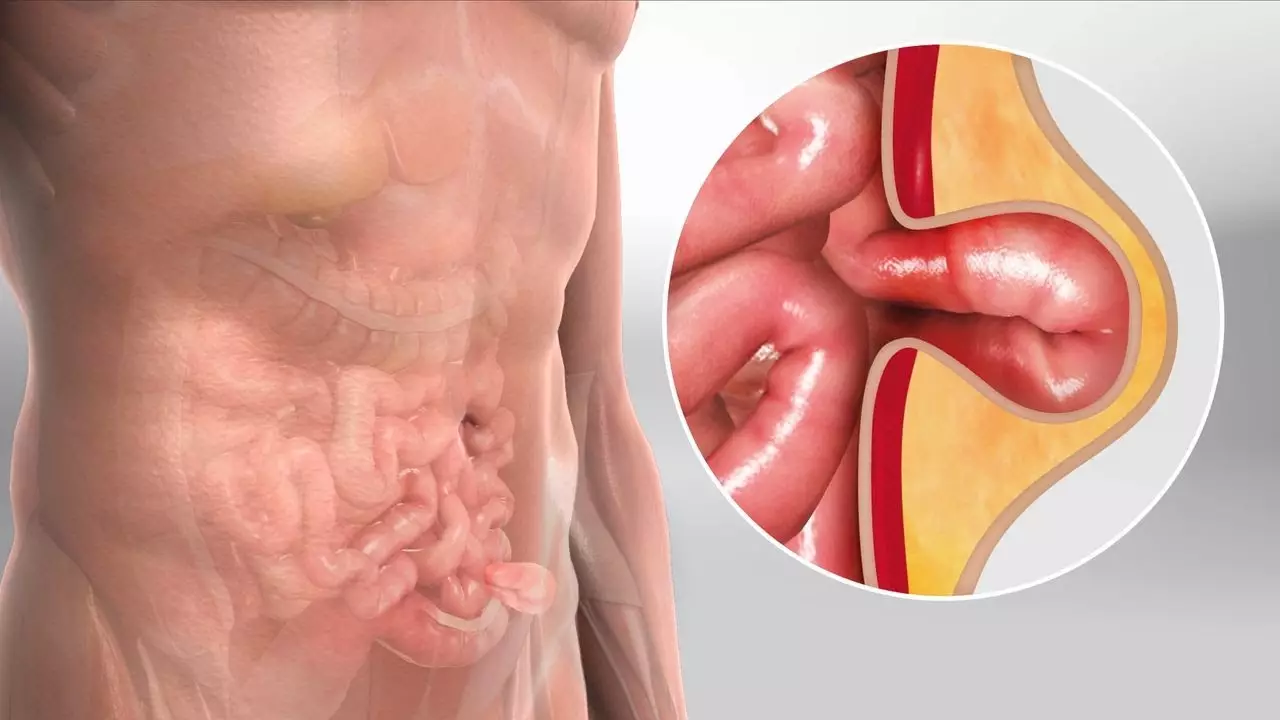

Hernia: ¿Qué es?